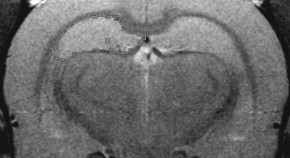

Peptide hormones such as oxytocin and vasopressin influence social behaviour in several mammalian species. Here it is shown that a population of interneurons in the rat olfactory bulb releases vasopressin, and that vasopressin signalling is required in the olfactory system for proper social recognition in rats. Although vasopressin may not work in exactly the same way in humans, social recognition mediated by experience-dependent vasopressin release may be common.